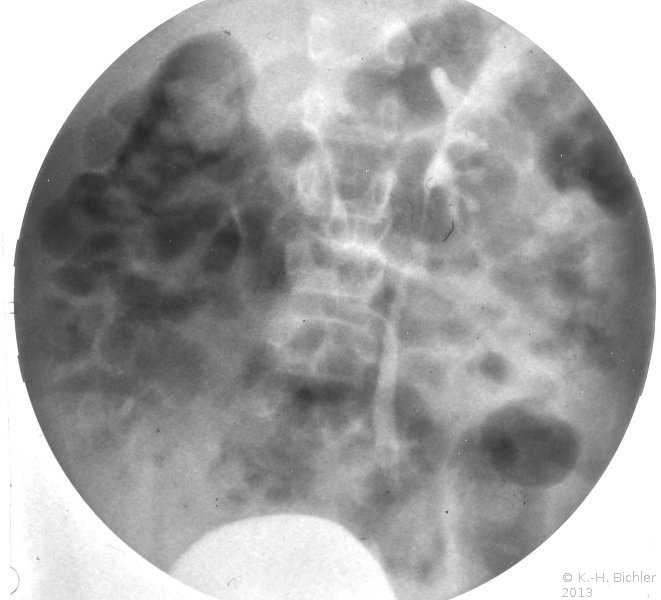

Die Refluxnephropathie ist von einer fortschreitenden Destruktion des Nierenparenchyms geprägt (Abbildung 7). Die pathologischen Veränderungen sind dabei abhängig vom Grad des Refluxes und oder der bakteriellen Infektion.

Die Nieren sind klein und haben ein Gewicht von ca. 40g. Die Nierenoberfläche ist diffus-höckrig. Refluxnarben finden sich an den Polen und der Mitte des Organs. Auf der Schnittfläche zeigt sich das Parenchym reduziert, z.T. mit abgeflachten Papillen und Bildung von Exkavationen bzw. Rezessi (Abbildung 7,8,9)

Beispiele Nieren mit ausgeprägter Refluxnephropathie.